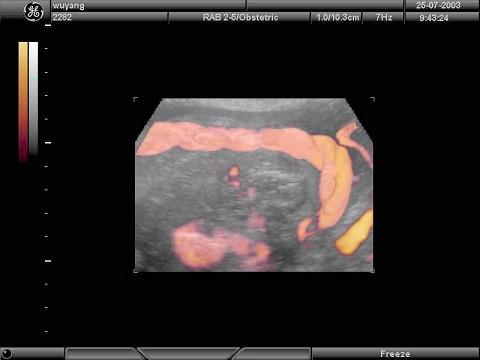

根据胎儿三维超声声像图,图中结构为?(?)A.脐带B.胎盘C.母体血管D.胎儿肢体E.羊膜

问题 根据胎儿三维超声声像图,图中结构为?(?)

选项 A.脐带 B.胎盘 C.母体血管 D.胎儿肢体 E.羊膜

答案 A